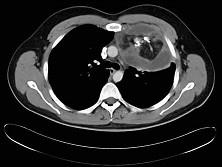

20岁,男,左胸痛伴压迫感,咳嗽一个月,请结合CT检查选出最可能的诊断 ( )A、脂肪瘤B、淋巴瘤C、纵隔血肿D、畸胎瘤E、胸腺瘤

问题 20岁,男,左胸痛伴压迫感,咳嗽一个月,请结合CT检查选出最可能的诊断 ( )

选项 A、脂肪瘤 B、淋巴瘤 C、纵隔血肿 D、畸胎瘤 E、胸腺瘤

答案 D